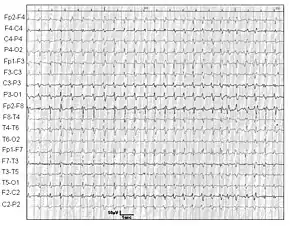

- A normal or an abnormal EEG, but not the diagnostic EEG changes often seen in classic CJD.[2]